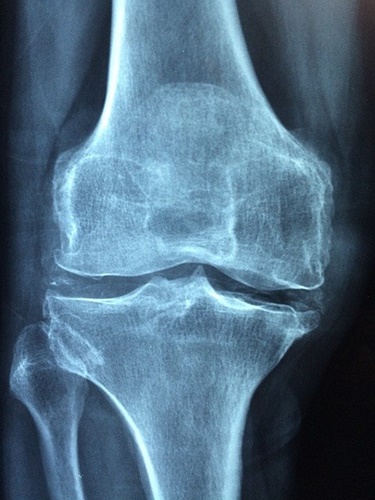

โรคข้อเข่าเสื่อม คือ

โรคที่เกิดจากการสึกกร่อนของกระดูกอ่อนผิวข้อ

ซึ่งเป็นผลมาจากอายุที่เพิ่มขึ้นและการใช้งานมาก

เมื่อมีการใช้งานผิวข้อที่สึกจะมีการขัดสีกัน ทำให้เกิดอาการปวดข้อเข่าตามมาโดยอาการข้อเข่าอักเสบและข้อเข่าเสื่อมสามารถเกิดขึ้นได้จากหลายสาเหตุดังนี้